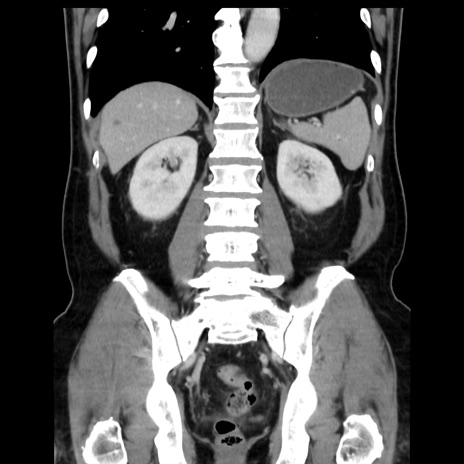

症例16(冠状断像)

【症例】 70歳代男性

【主訴】 腹痛、嘔吐

【現病歴】 約1ヶ月前より間欠的に腹痛と嘔吐あり、当院消化器内科を受診したところCTで多発する肝臓のLDAを指摘され、精査中であった。以降は消化器症状は安定していたが、2日前より嘔気と腹痛があり、同日より排便・排ガスが消失した。改善認めず、 本日、救急外来を受診した。